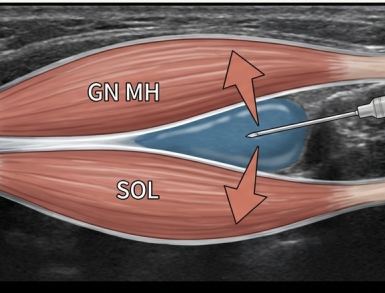

그 다음은 근막 통증 증후군입니다. 아킬레스건의 근육인 비복근(Gastrocnemius)과 가자미근(Soleus)의 길이가 짧아지면서, 아킬레스건을 잡아당기는 스트레스가 누적됩니다. 이러한 근육 긴장으로 근막통증증후군(MPS)이 유발될 수 있습니다.

한의학에서 근육, 근막은 "경근"이라고 하는데요. 눌렀을 때 가장 통증이 심한 혈자리를 찾아서 근육 사이 근막층에 약침을 주사하여 유착을 떼어냅니다. > 3단계: 신생혈관 신경성 염증 > > 만성 통증의 원인